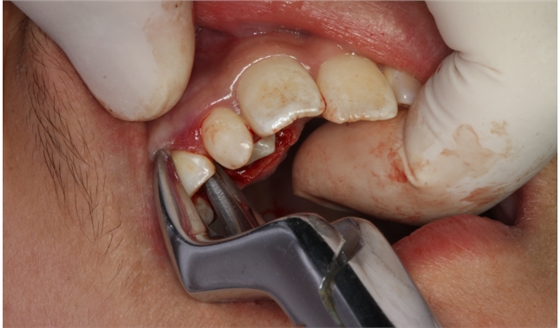

圖10.拔除右側(cè)乳尖牙